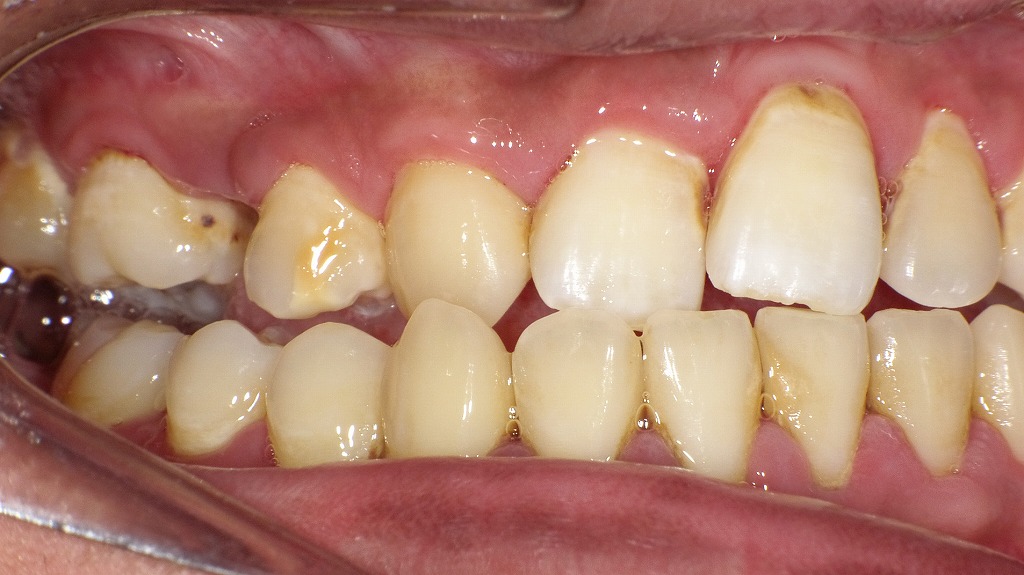

② 歯ぐきの炎症(歯周病・歯槽膿漏)

歯周病が進行すると、歯ぐきの中で膿がたまり、局所的に腫れることがあります。

特に「歯ぐきの一部がぷっくりして痛い」「押すと膿が出る」場合は、歯周病性の腫れが疑われます。

歯面には歯石やプラークが沈着し、歯ぐきには発赤・腫脹がみられます。これは歯周病が進行した状態で、歯周ポケットの内部で細菌が増えることで炎症が悪化し、周囲の組織に膿が溜まると頬が腫れる原因になります。放置すると骨の破壊が進み、歯槽膿漏へ移行することもあるため、早期の治療と専門的クリーニングが重要です。

歯のクリーニング(PMTC)による着色・歯石除去症例

日常の歯みがきでは落としきれない歯石や着色を、専用の器具を用いた歯科クリーニングで除去した症例です。術前では歯の表面や歯の間に歯石やステインの付着が確認されますが、クリーニング後は歯面が滑沢になり、本来の歯の色調に近い自然な明るさを取り戻しています。